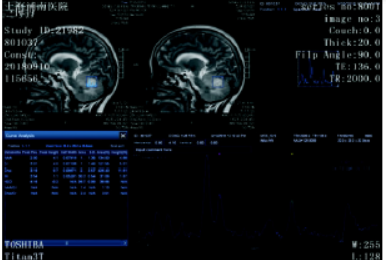

图2 患者的MRS提示:NAA明显下降,Cho明显升高

PCNSL典型的临床表现主要是逐渐进展的局灶性症状,包括颅内压增高、局灶性神经功能缺损、精神状态改变;有少量文献报道,病变可侵及眼球,引起视力下降、视物模糊等症状。PCNSTL的临床表现及预后与PCNSL是相类似的。PCNSL的磁共振表现为单发或者多发病灶,T1WI表现为脑灰质样的等信号或者稍低信号,T2WI表现为等信号或稍高信号;DWI及ADC图上表现为扩散受限的改变,即DWI稍高信号,ADC值下降;MRS表现为NAA峰值变低,并可见脂质峰;增强扫描表现为明显的均匀强化;瘤周水肿与肿瘤的大小不成比例,一般瘤周水肿和占位效应较轻。